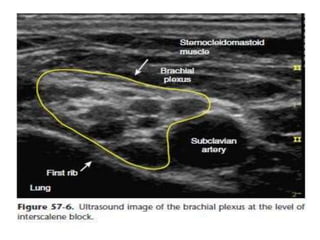

ULTRASOUND GUIDED

 A supraclavicular view of the subclavian artery &

brachial plexus is obtained & the plexus is traced up

the neck with the probe until the plexus trunks are

visualized as hypoechoic structures between

anterior and medial scalene muscles.

 The needle is then advanced either in an “out-of-

plane” or an “in-plane” approach.

 After –ve aspiration , local anaesthetic is infiltrated

into brachial plexus.

 Small volume is required.